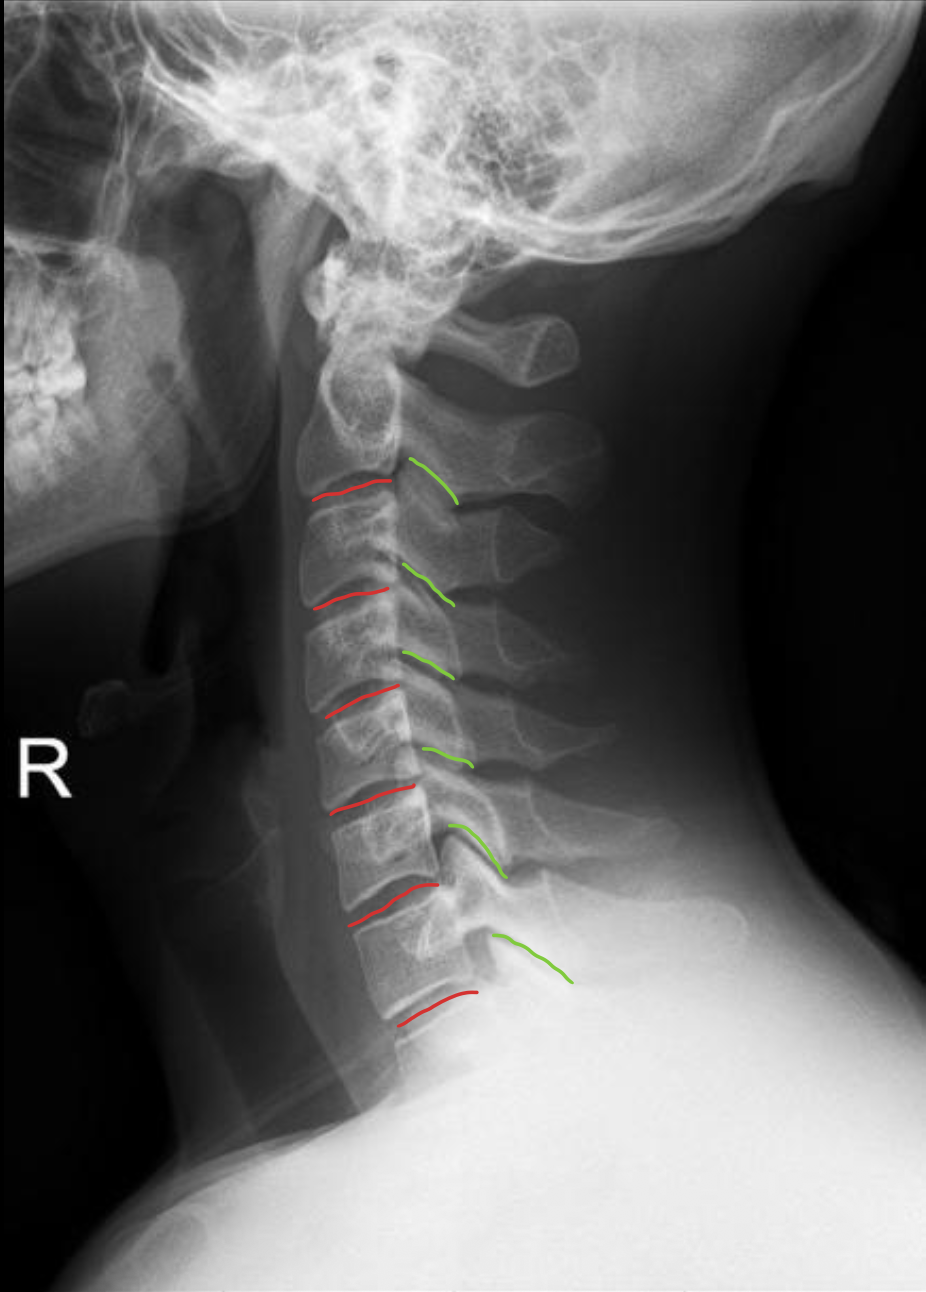

C1

C2

C3

C4

C5

C6

C7

T1

1st rib

椎板棘突线(椎弓后缘线)

Spinolaminar

棘突后缘线

Posterior spinous